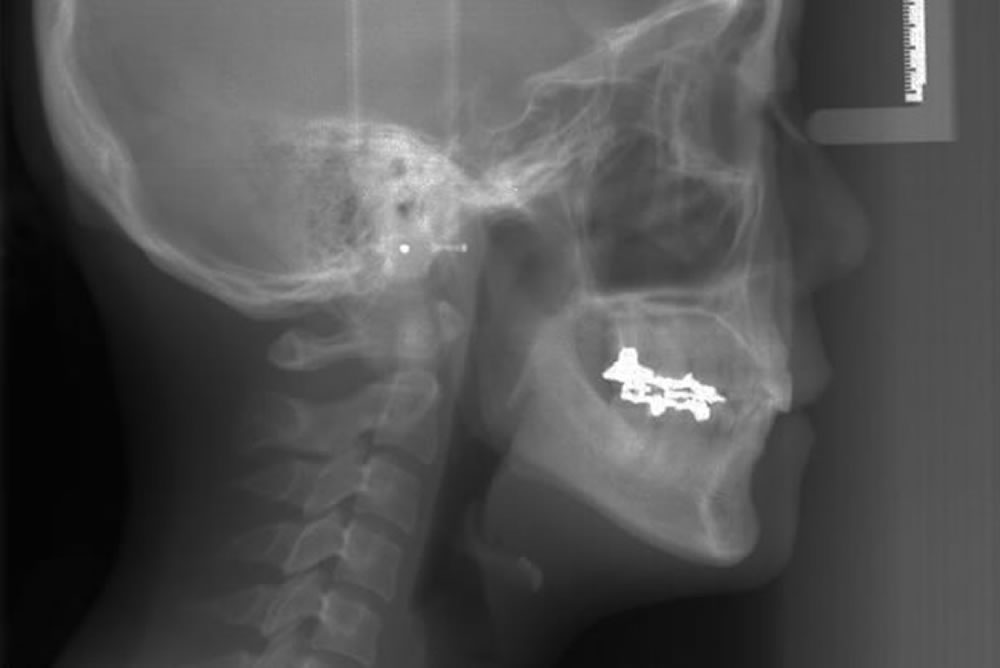

矯正治療用の精密レントゲン「セファロ」の活用

当院では、「セファロ」と呼ばれる矯正治療専用のレントゲンを使用していますので、歯と顎と顔全体のバランスを同年代の平均的なものと厳密に比較分析することができます。顎骨全体を診断するのに非常に有効です。